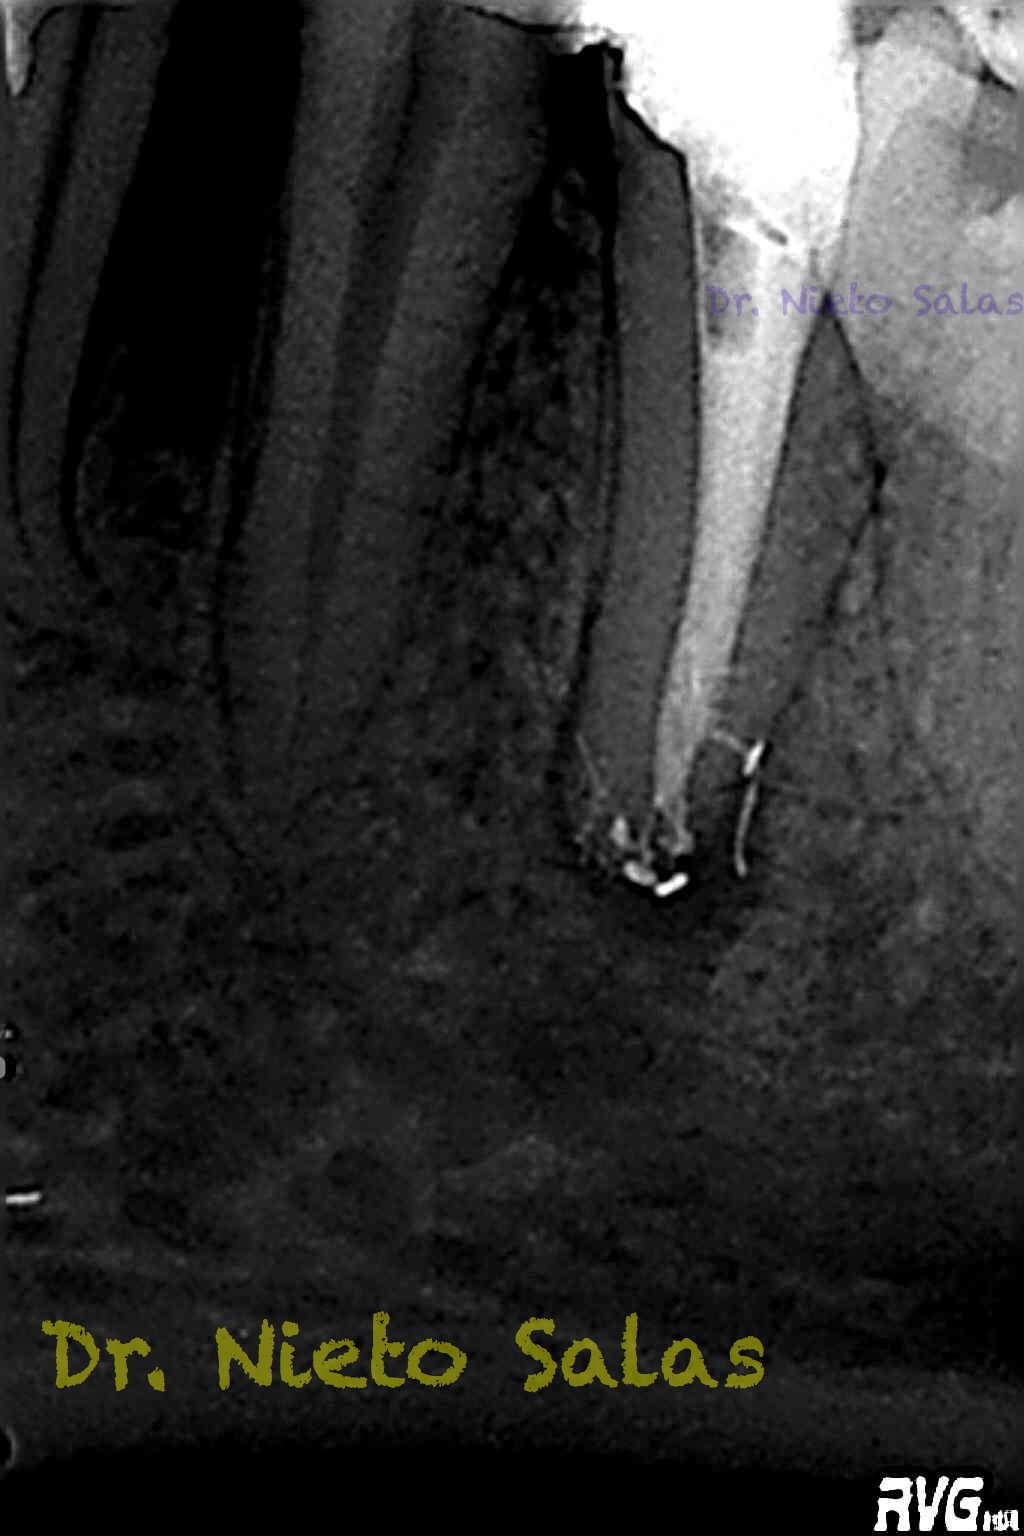

Una vez que hemos desbridado biomecánicamente con limas de muy pequeño diámetro, obturamos:

Y este sería el otro caso:

Es muy importante cambiar la proyección de las Rx para tener más información de como hemos sellado el sistema de conductos.